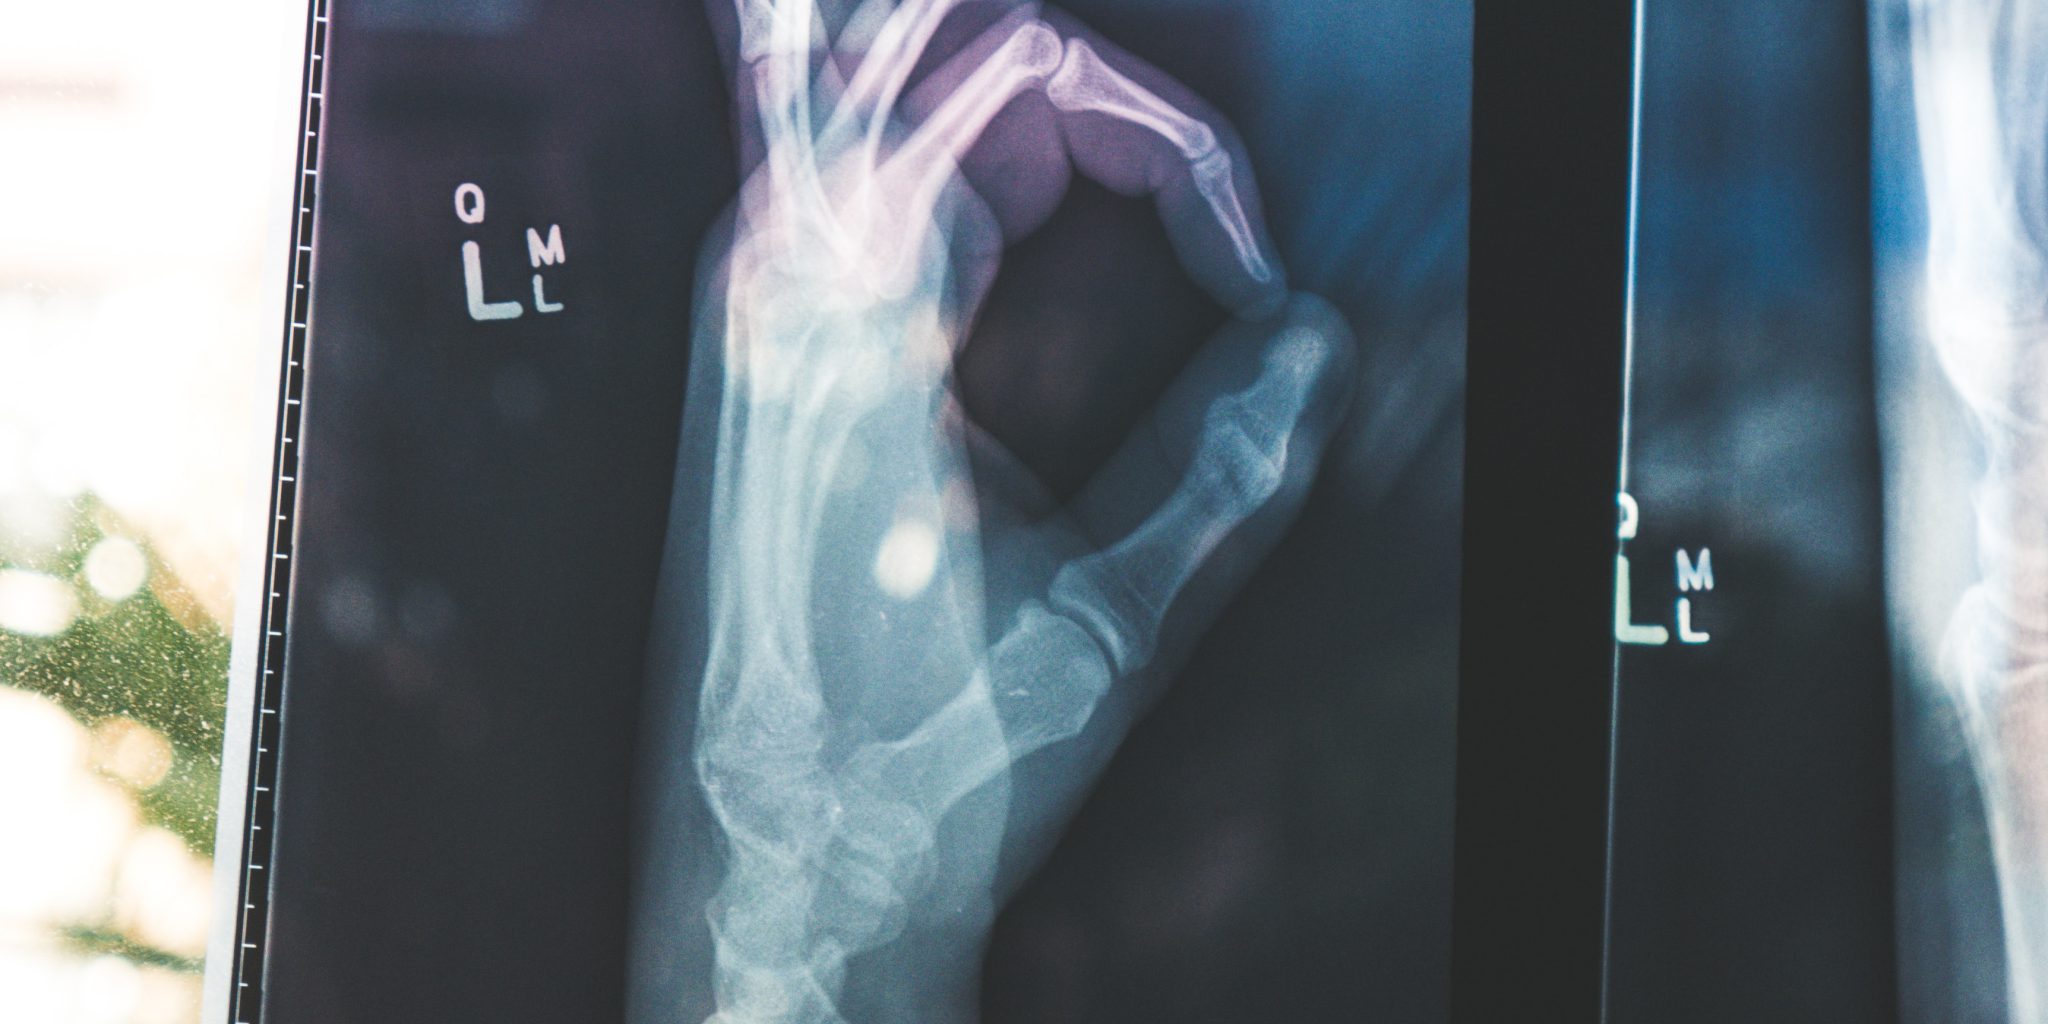

Nowadays, most individual patient records have been digitized removing the need for paper files and are referred to as electronic health records (EHRs). The adoption of EHR has encouraged the sharing of patient information among clinicians to lower costs, speed diagnosis, and improve patient outcomes. Professionals are then able to analyze these mass records to predict health outcomes based on trends, to track a treatment’s effectiveness, and to even research which factors could be leading to disease and cancer diagnosis.